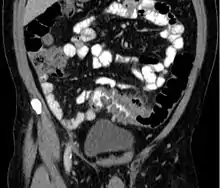

People with the above symptoms are commonly studied with computed tomography, or a CT scan.[12] The CT scan is very accurate (98%) in diagnosing diverticulitis. In order to extract the most information possible about the person's condition, thin section (5 mm) transverse images are obtained through the entire abdomen and pelvis after oral and intravascular contrast have been administered. Images reveal localized colon wall thickening, with inflammation extending into the fat surrounding the colon.[13] The diagnosis of acute diverticulitis is made confidently when the involved segment contains diverticula.[14] CT may also identify people with more complicated diverticulitis, such as those with an associated abscess. It may even allow for radiologically guided drainage of an associated abscess, sparing a person from immediate surgical intervention.